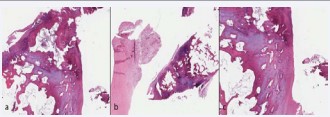

A 44 year old patient, male suffering from rheumatoid arthritis, complaining pain and clamping of the right knee for 5 years during the daily routine activities, with no associated trauma. The patient presents with a history of physiotherapy treatment and two arthroscopic procedures, with no improvement of symptoms. Radiographic examination revealed an image consistent with an intra-articular loose body in the medial compartment, in the topography of the posterior horn of the meniscus (Figure 1). The Magnetic Resonance Imaging (MRI) enabled the identification of bone tissue internal to the posterior horn of the medial meniscus (Figure 2). The surgical treatment was performed by arthroscopy via inter condylar access through the anterolateral and anteromedial portals (Figure 3) to position the optics and visualization of the posterior compartment (Figure 4). We identified the mensicalossicle adjacent to the posterior horn of the medial meniscus (Figure 5) and performed its removal utilizing basket forceps associated with economic resection of the posterior horn of the meniscus, due to the intimate anatomic relation between the two structures (Figures 6,7). The material was subjected to histopathological analysis, which identified fragments of meniscus containing hyaline alterations and metaplastic ossification, apart from a degenerative process, fibrosis, and foci of neovascularization (Figure 8). The patient evolved satisfactorily, with complete recovery of the range of motion and absence of joint locking symptoms, being that his last clinical evaluation was done with 3 months of postoperative. The last X-ray showed the absence of the bone body on the posterior compartment of the knee (Figure 9).

Figure 8: Histologic cuts of the meniscal fragments shows hyaline alterations and metaplastic ossification, apart from a degenerative process, fibrosis, and foci of neovascularization (hematoxylin-eosin).